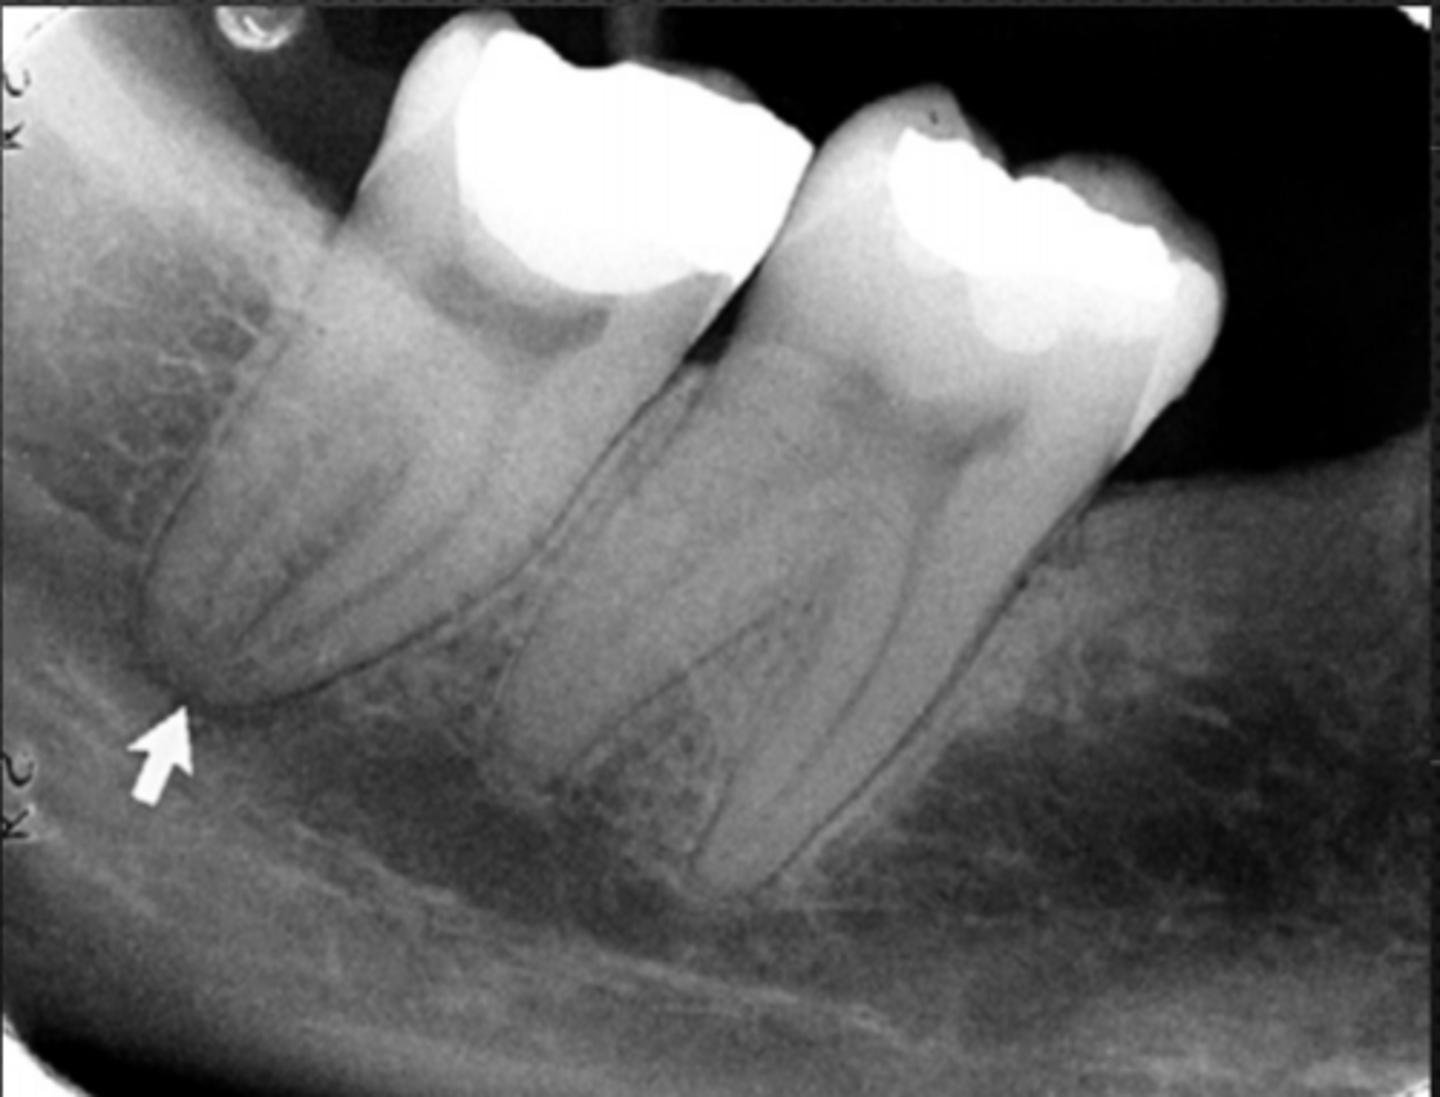

anterior border of the ramus

Name the structure the white arrow is pointing to.

<p>Name the structure the white arrow is pointing to.</p>

internal oblique ridge or mylohyoid ridge

Name structure the black arrow is pointing to.

<p>Name structure the black arrow is pointing to.</p>